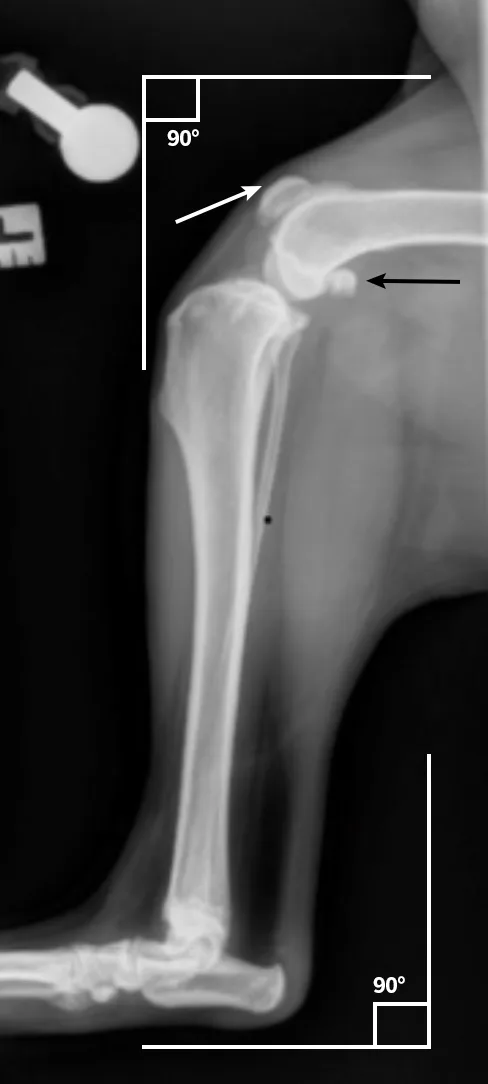

Place the patient in lateral recumbency with the affected limb on the table. Hold the limb or use positioning tools to keep the stifle and hock at a 90-degree angle. If needed, use gauze or a foam pad to elevate the tarsus and ensure the stifle joint does not rotate. Abduct the unaffected limb up and away from the table toward the patient’s back.

This positioning is ideal for planning some stifle surgeries (eg, tibial plateau-leveling osteotomy). For some procedures (eg, tibial tuberosity advancement), extending the stifle to a standing angle (≈135 degrees) is preferred.

Center the collimator beam over the tibia to include both the stifle and tarsal joint.

Author Insight

On the radiograph, the stifle and tarsus should be at an »90-degree angle. The patella should be cranial (white arrow), and the medial and lateral femoral condyles should be as superimposed as possible. The medial and lateral fabellae should have near superimposition to each other (black arrow).